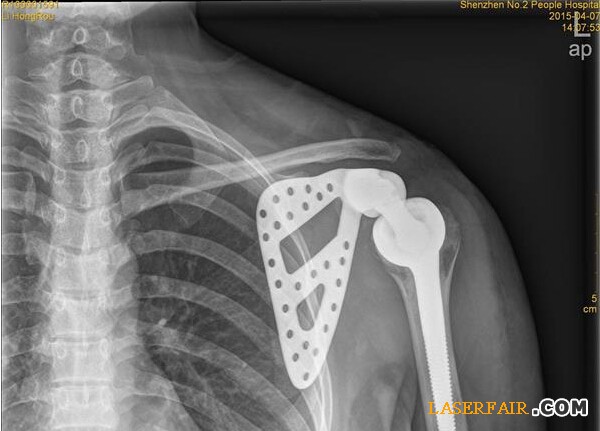

近日,深圳市第二人民醫(yī)院收治了一位27歲女患者,該患者肩胛部位的骨頭已經(jīng)被腫瘤侵蝕四分之三,亟需手術(shù)切除。但是如果貿(mào)然切掉整個肩關(guān)節(jié),不僅手術(shù)風(fēng)險大,恢復(fù)后病人生活也難以自理。于是該院利用3D打印技術(shù)制備出與患者肩胛骨完全匹配的鈦合金假體,置換掉原來腫瘤壞死的肩胛骨,打造了一個新的“肩膀”。

隨著3D技術(shù)的日臻成熟,該醫(yī)院與3D打印公司展開治療研究,針對李女士的治療首次采用3D打印技術(shù)制備出與患者肩胛骨完全一致的鈦合金假體,并成功植入骨腫瘤患者體內(nèi)。

“首先是3D打印人工制作肩胛骨模型,把采集到的李女士左邊肩胛骨大小、形狀等數(shù)據(jù)通過3D技術(shù)打印出完全吻合的模型。”深圳市第二人民醫(yī)院骨關(guān)節(jié)、骨腫瘤科副主任醫(yī)師譚紀(jì)鋒介紹,然后根據(jù)模型設(shè)計出手術(shù)方案,在模型上標(biāo)注手術(shù)的螺釘孔、切除邊界,實現(xiàn)手術(shù)精準(zhǔn)化。”由于3D模型采用的樹脂材料不能直接植入人體內(nèi),因此醫(yī)院將模型送至人工關(guān)節(jié)制作廠,制作出鈦合金人工肩胛骨。在為李女士進行腫瘤完整切除后,再將鈦合金人工肩胛骨植入患者體內(nèi)。由于3D打印實現(xiàn)了“量體裁衣”,因而鈦合金人工肩胛骨能實現(xiàn)精準(zhǔn)匹配。

14日,記者從醫(yī)院獲悉,李女士的手術(shù)很成功,很快就可以出院了。據(jù)了解,這是深圳乃至華南地區(qū)首例肩胛骨3D打印鈦合金假體植入術(shù)。